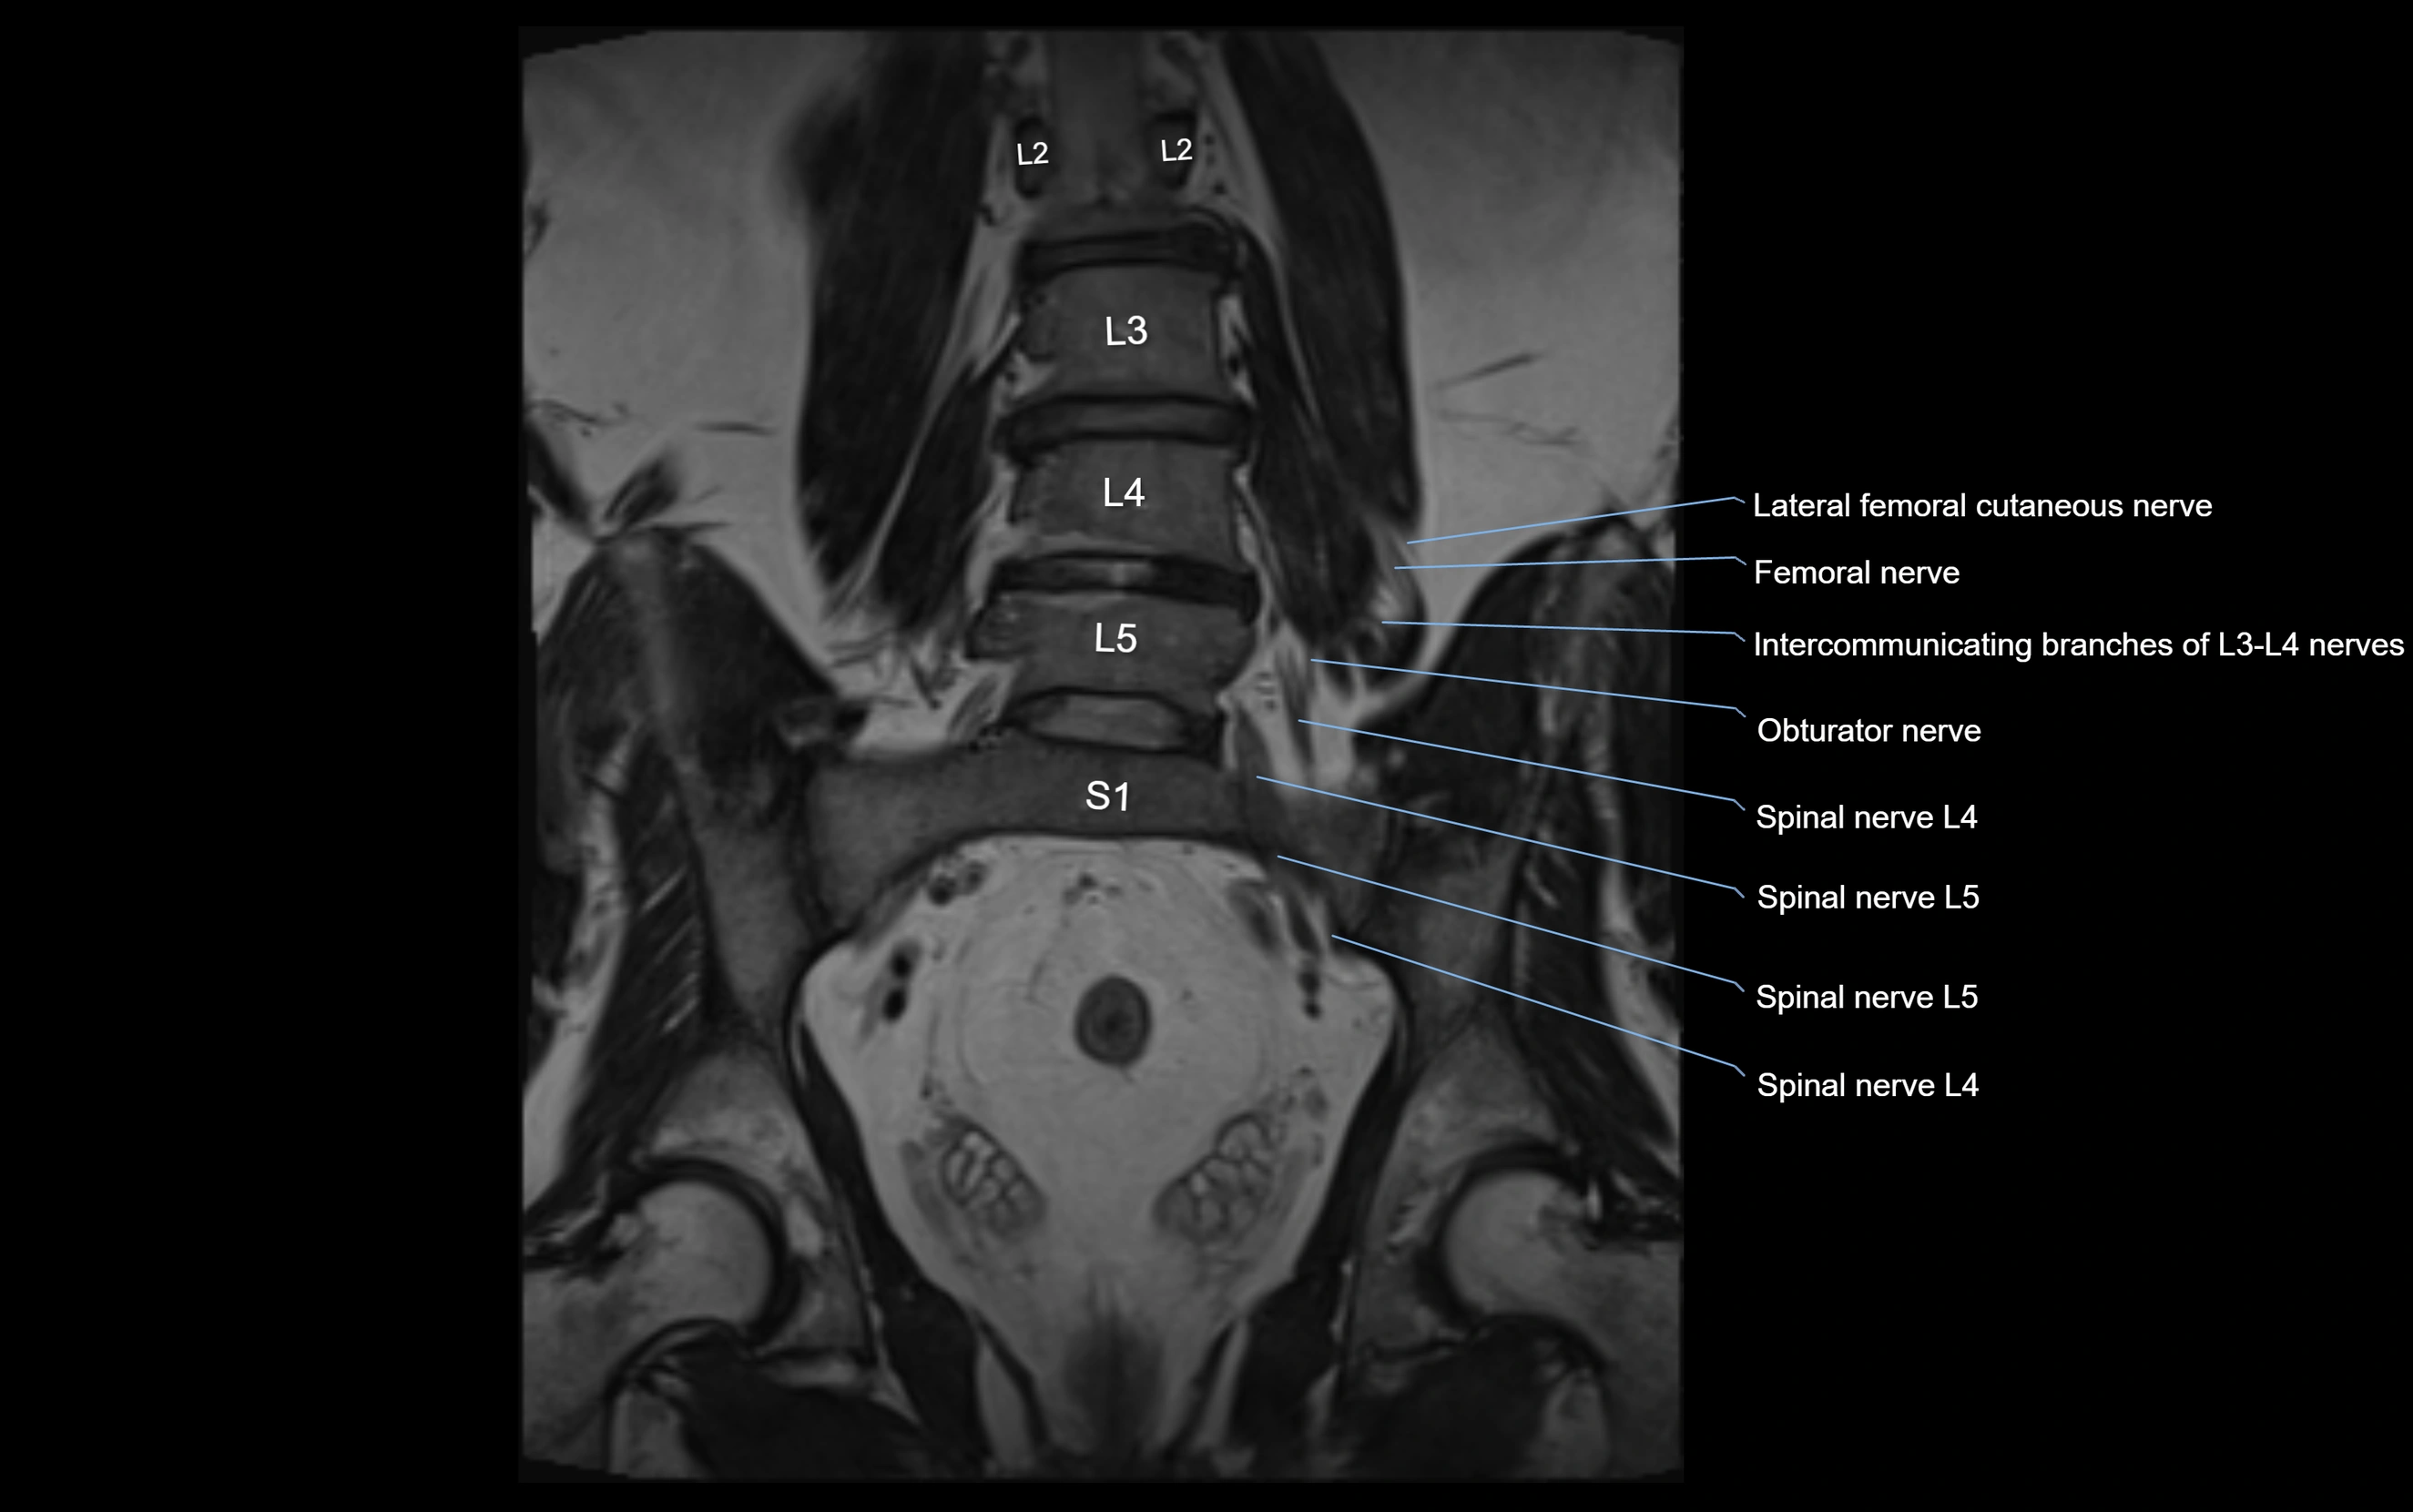

MRI image

image